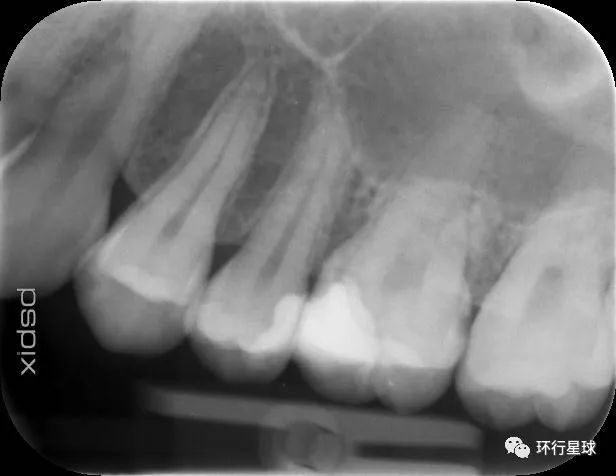

我的龋齿牙片

智齿是许多留学生的一大烦恼,根据拔除难度的不同,价格也不尽相同。

需要注意的是,在欧洲牙科诊所的医生根据专业不同分化程度很高,普通牙医不负责智齿的拔除,甚至也不负责根管治疗,需要找专门的stomatologist 或者endodontiste。

如果学校设有校医院,拔除智齿的价格可能低至50欧元,但如果前往私立诊所,价格可能在150到500欧不等。

值得一提的是,在西欧国家里,法国的牙医诊所价格相对低廉,以根管治疗为例,在法国仅需400欧,而在德国私立牙科诊所可能收取高达2000欧的费用。